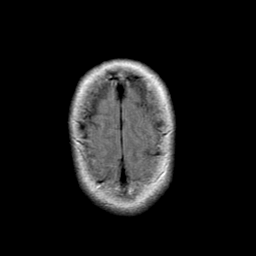

Stroke: proton density-weighted MR #1 -- Slice #22

[Home][Help][Clinical] Slice 22